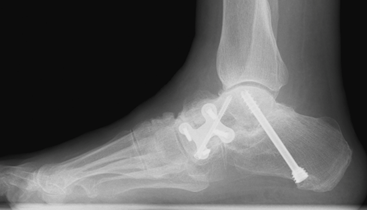

These X-rays show the foot from the side with initially a loss of arch height and a midfoot sag, in a young adult. Post procedure the lateral column has been lengthened using an Evans procedure with a navicular cuneiform fusion.

This has now been successfully realigned.